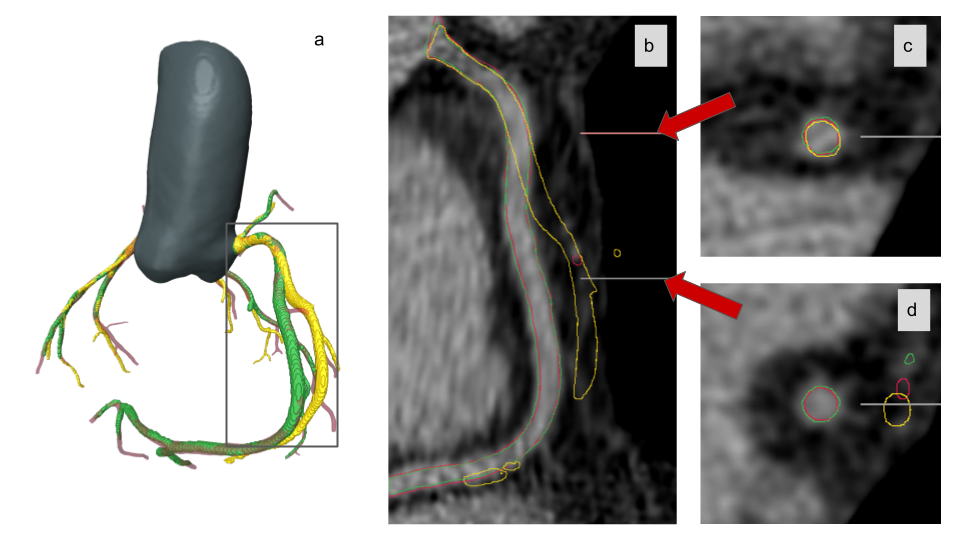

Refer to caption

Figure 5: Example of a mismatch between the GT created based on registration (\mdblksquare\mdblksquare\mdblksquare), the inference of the neural network (\mdblksquare\mdblksquare\mdblksquare), and the manually aligned contrast GT (\mdblksquare\mdblksquare\mdblksquare) in the distal part of RCA (a), juxtaposed with the corresponding non-contrast CT scan. Panel (b) is a CPR projection along the vessel centerline indicated in (a) by a solid black rectangle. Panels (c) and (d) show cuts in the vessel’s short axis at two distinct points. Based on the visual comparison, we can note that the inference of the deep model and manually aligned vessel are consistent with the image, unlike the GT used in the training process.

With a mean validation set’s Dice at the level of 0.57±0.10plus-or-minus0.570.100.57\pm 0.10, the segmentation accuracy is relatively low compared to the best methods for segmentation of coronary arteries based on contrast CT, reaching Dice scores up to 0.88 [10]666Although we are aware that confronting different algorithms over different datasets (and training-test splits) may easily become misleading, we can indeed observe that the Dice scores are significantly larger for contrast CT scans.. However, there are two important aspects which should be noted here. First, for coronary arteries, being very thin structures, the Dice metric decreases substantially even in case of small errors on the voxel level, which also results in low interrater Dice for this type of segmentation problems. The information contained in the non-contrast CT scan is far more scarce than in contrast CT, which naturally leads to higher segmentation errors as well. Secondly, and more importantly, the metrics presented here are calculated on a validation set consisting of semi-automatically generated GT. The sole criterion used in the selection of CT scans accepted in our study for the training set and the validation set was the alignment of the proximal regions of the coronary arteries. Therefore, the lower Dice scores observed in this case may be attributed to the lower quality of the GT data in the distal regions. This issue is illustrated in Fig. 5, which shows that segmentation of the distal part of RCA based on the trained model is more consistent with the CT scan than the GT used for training. Indeed, in some cases, the inference of the model is better than the underlying GT used for both training and validation, which is counter-intuitive, but can be justified by the strong regularization imposed on the U-Net model. The network learns robust filters to detect vessels from those parts of the dataset where registration is correct and is not degraded by misinformation caused by massive but relatively rare misalignments. Fig. 5 is a prominent example that the model is more accurate than the GT used for its training.